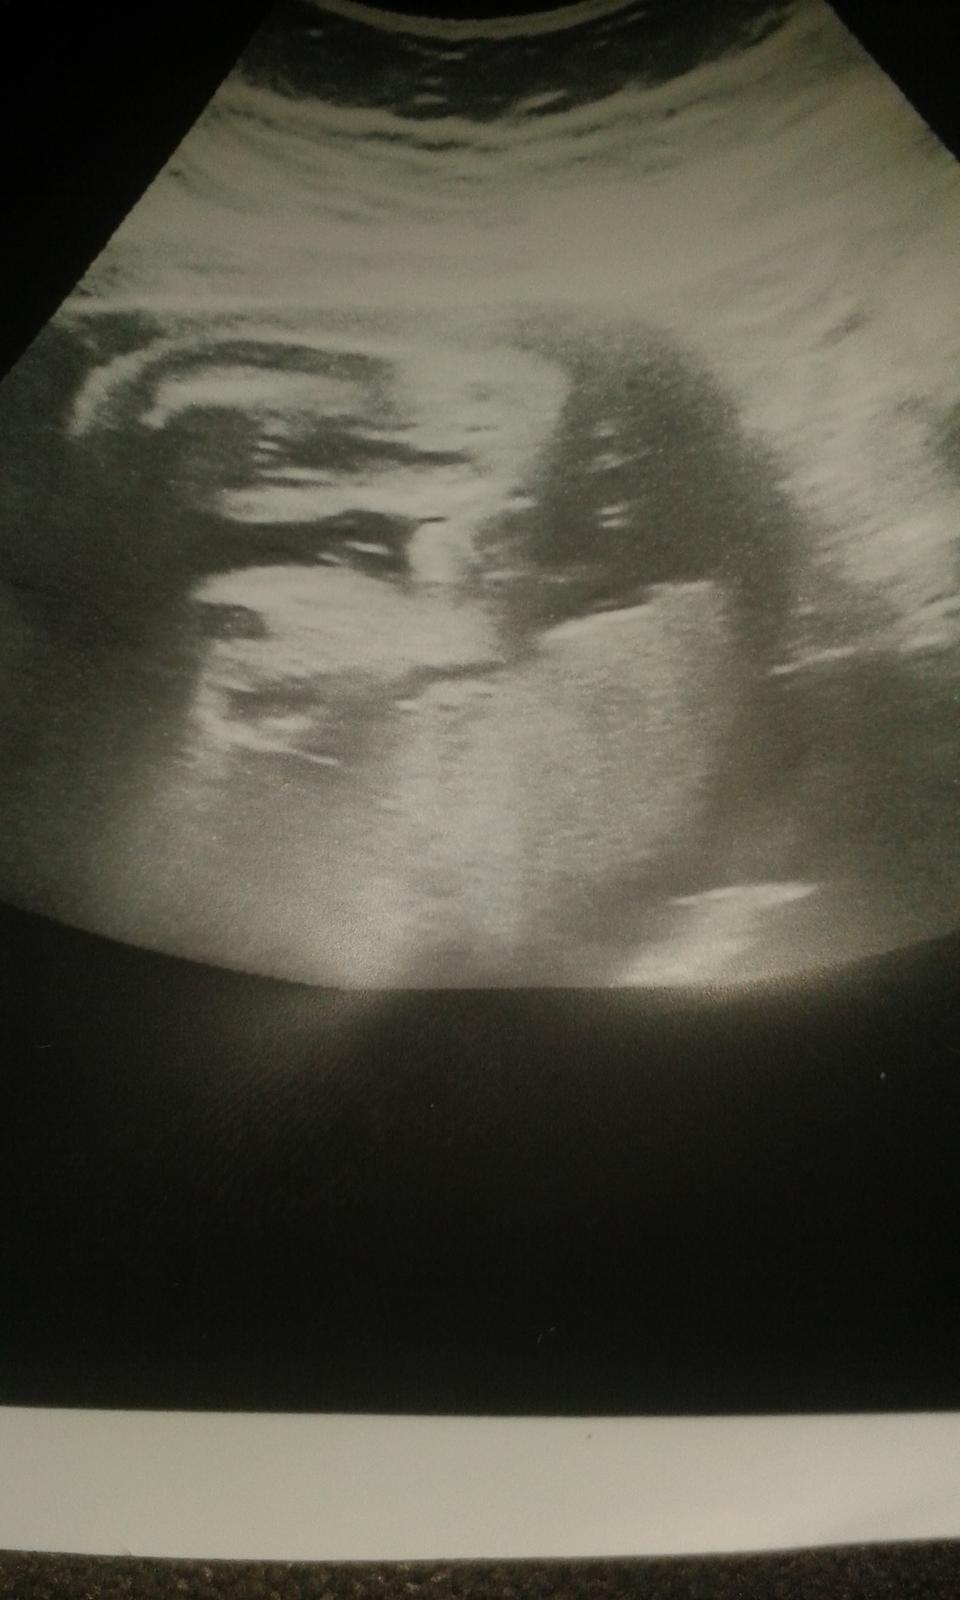

Ahoj holky, chci se zeptat..copak vidite na fotce za pohlavi?? Dekujii 🙂